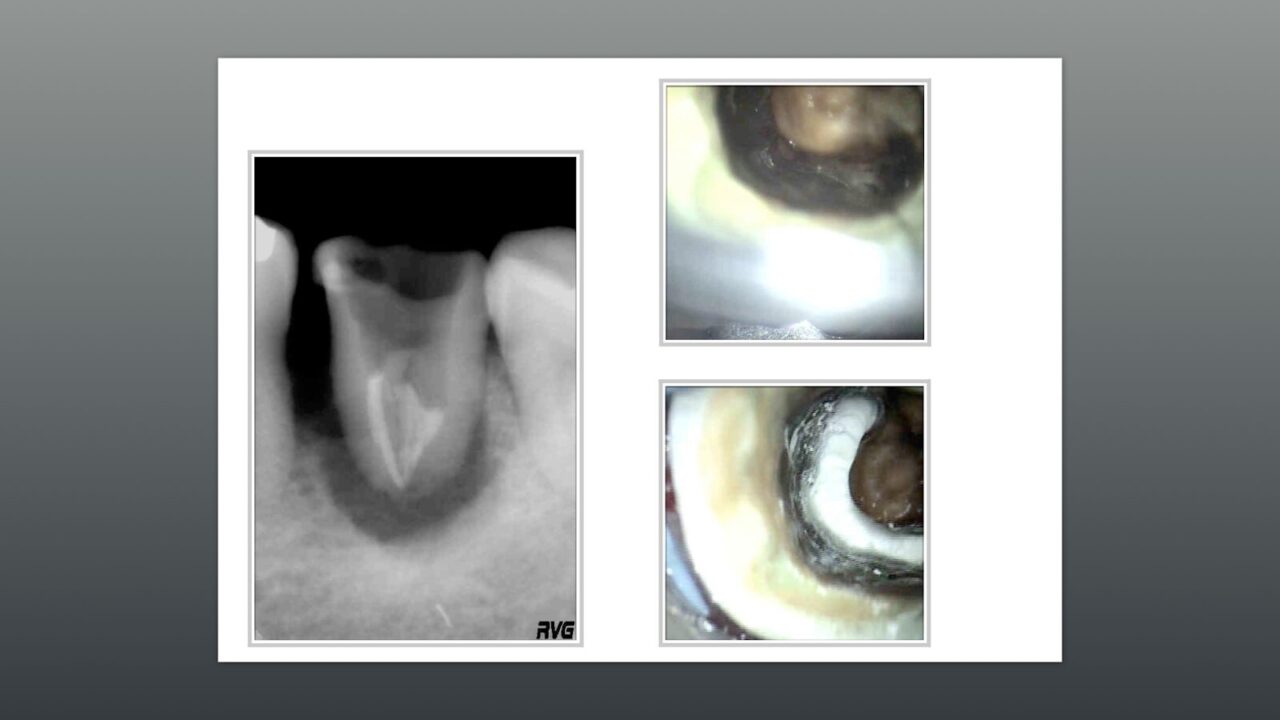

術前のレントゲン写真から歯根破折を右派が割れるレントゲン透過像を確認できます。

また患者の主訴は、頬から膿が出る事が5年以上前より続いている事から、都内の大学病院を数件行ったが、一向に治らず、根管治療の吉松歯科医院の以前のホームページを見て来院に至りました。

初診時のコンサルテーション後に次回より根管治療を行いました。

明らかな破折線を認め、1回治療バイオセラミックスよる根管充填、ファイバーコアによるコアまで行いました。

術前のレントゲン写真と破折線の写真、根管充填後の写真。

歯冠から根尖部に向かう明らかな破折線を認めました。(この症例は2010年のものなので写真の解像度が当時のものであるため低いです。)